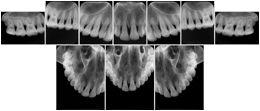

3. A dental provider wishes to capture a series of DICOM IO images for the patient’s dentition. The tooth morphology, teeth are divided into molars, premolars, canines and incisors, and a number of images for each jaw. The anatomic information was captured utilizing the triplet of schema. This standard code sequence is based on ISO 3950-2010, Dentistry - Designation system for teeth and areas of the oral cavity.

Every IO image should have anatomic information either through the primary or modifier sequence.

In most standard cases, images are oriented in structured layouts. These structured displays are useful to be shared between providers for reference purposes.

Table OO.1.1-1 shows structured display standard templates, where Viewset ID is based on the Japanese Society for Oral and Maxillofacial Radiology (JSOMR) classification provided by JIRA (Japan Medical Imaging and Radiological Systems Industries Association, www.jira-net.or.jp). Expected or typical teeth to be imaged location, region and designation codes are based on ISO 3950-2010, Dentistry - Designation system for teeth and areas of the oral cavity. For all the hanging protocols listed in OO.1.1-1, the value to use for Hanging Protocol Creator (0072,0008) is "JSOMR" and the value to use for Hanging Protocol Name (0072,0002) does not include "JSOMR" (e.g., "DL-S001A", not "JSOMR DL-S001A").